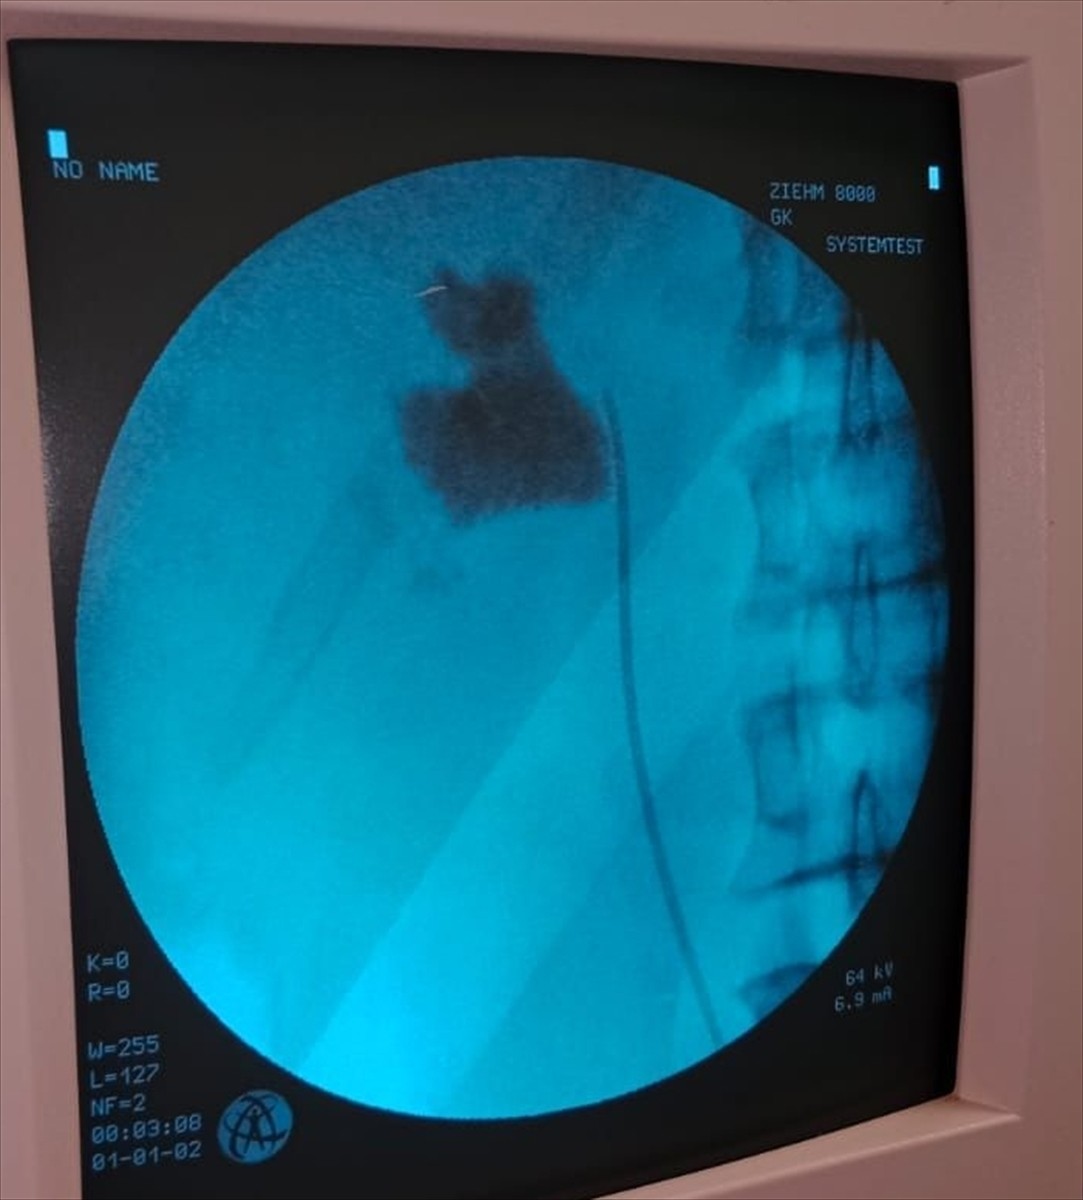

Kırşehir'de, Eğitim ve Araştırma Hastanesi'nde bir hastanın böbreğindeki 6 santimetrelik taş, kapalı ameliyat yöntemiyle alındı.

Hastaneye başvuran İlhami Çakır'ın yapılan kontrollerinde, sol böbreğinde 6 cm boyutunda bir taş tespit edildi. Üroloji Kliniği'nden Uzm. Dr. Talip Göktaş ve ekibi, kapalı böbrek taşı yöntemi PNL ile başarılı bir ameliyat gerçekleştirdi.

Ameliyat sonrası bir gün içinde taburcu olan Çakır, operasyon ekibine teşekkür etti. Uzm. Dr. Göktaş, hastaların bu yöntemle açık ameliyatlara göre daha hızlı bir iyileşme süreci yaşadığını belirterek, "Hastamız 1 gün sonra taburcu edildi. Bu yöntemle hastalarımız daha konforlu bir şekilde süreç atlatabiliyor. Son 5 yıl içinde hastanemizde 50'nin üzerinde bu tarz başarılı ameliyat gerçekleştirdik," ifadesini kullandı.